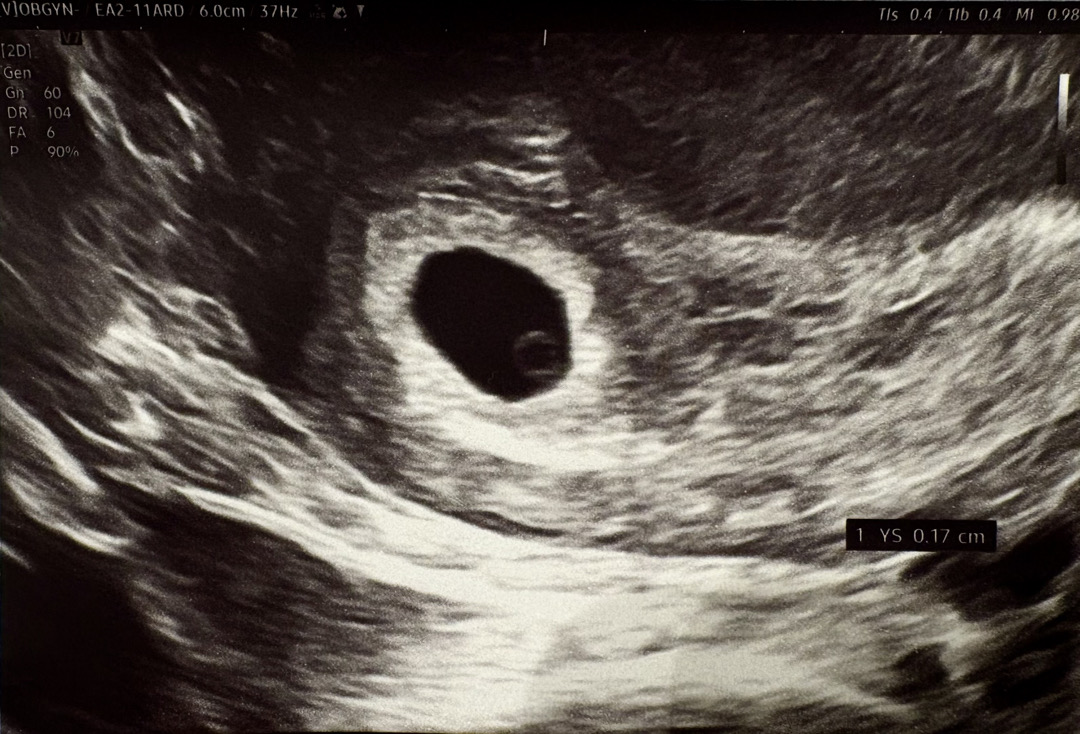

5주 1일차 난황 보고 왔어요~😆

아기집만 보일줄 알았는데 난황까지 봤어요~ 5주 3~4일차로 보인다고 했어요~ 빨리 심장소리 듣고싶어요